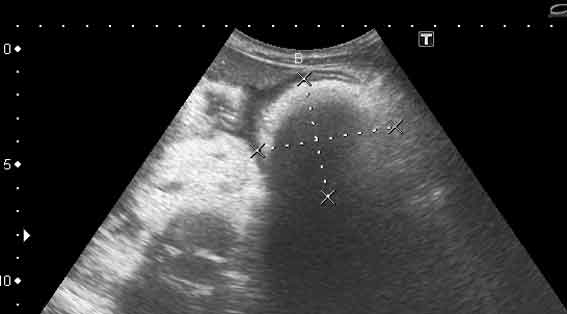

УЗИ, трихобезоар желудка. Gastric trichobesoar, ultrasonography.

Наблюдение наших коллег, работающих в педиатрии (valeriy.andilevko).

УЗИ, девочка 8 лет с ментальными расстройствами.

Безоар, проглоченный предмет ИМХО

Да, трихобезоар.